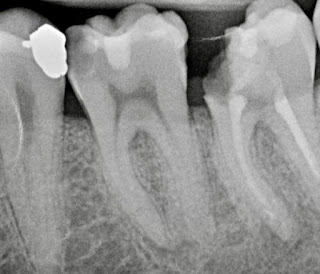

Caso clínico Máster: necropulpectomía en 14

Caso clínico Máster: Reimplante en 44

Caso Clínico Máster: Endodoncia 11 con Biocerámico

Caso clínico Máster: Biopulpectomía 36